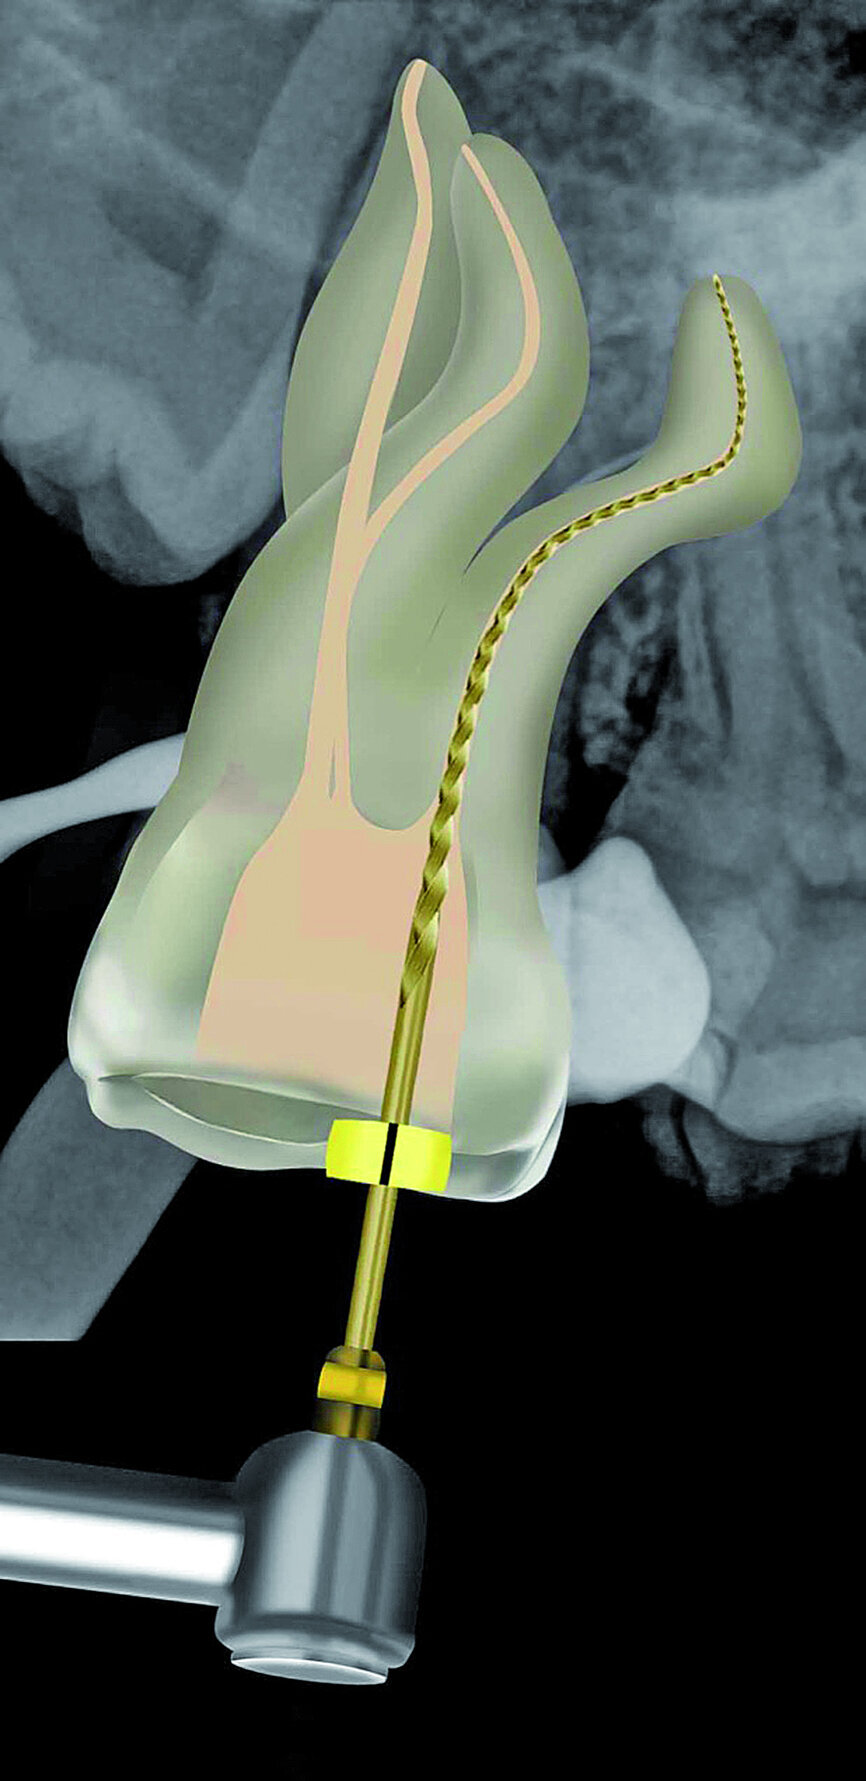

Fig. 21: A size 08 K-File in the M4 reciprocating handpiece was used to initiate the preparation of a reproducible micro glide path.

The pulp chamber was filled with Glyde (Dentsply Sirona) before the canals were carefully negotiated to full working using pre-curved size 08 K-Files (Fig. 19). Working length measurements obtained from an electronic apex locator reading corresponded with the lengths obtained from the 3D Endo Software. These measurements were also confirmed radiographically (Fig. 20). A reproducible glide path was prepared in each root canal system with the size 08 K-File in an M4 Reciprocating handpiece (Sybron Endo; Fig. 21), followed by making a size 10 K-File ‘super loose’ (Fig. 22). A ProGlider (Dentsply Sirona) was used in a rotary motion to expand the glide path in the palatal root canal (Fig. 23). Considering the sharp and severe curvatures in the two buccal canals, it was decided to convert the ProGlider instrument into a manual file to expand the glide path in these tortuous canals with more safety (Fig. 24). The manually adapted ProGlider was used in a balanced force motion up to working length. In addition, to create more safety during the canal preparation of the two challenging buccal root canals, it was also decided to use the reciprocating WaveOne Gold Glider (Dentsply Sirona; Fig. 25), after the ProGlider instrument to further expand the glide paths. The WaveOne Gold Glider was used in 4–8 backstroke brushing motions from working length, in the two buccal root canal systems.